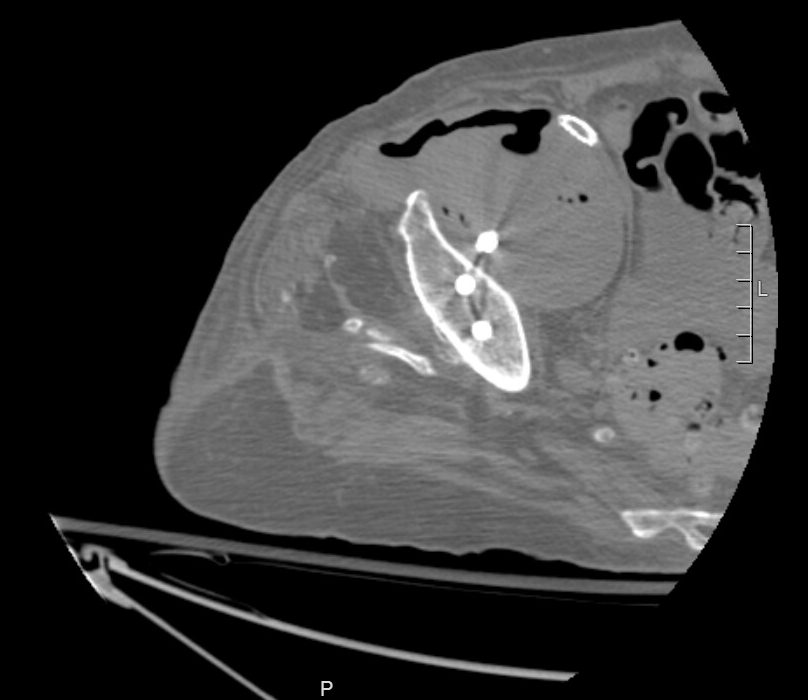

Un mese prima le avevano trovato un grande pseudoaneurisma all’altezza dell'arteria iliaca esterna. Sì, quella che si vede nell’immagine è una vite di una precedente sostituzione dell'anca che lo attraversa. Dopo uno stenting era tornata a casa.

Poiché era settica e dolorante, facemmo una nuova TC. La nuova TC mostrava una ampia formazione di gas all'interno dello pseudoaneurisma. Un’infezione, che rappresentava un gigantesco problema.